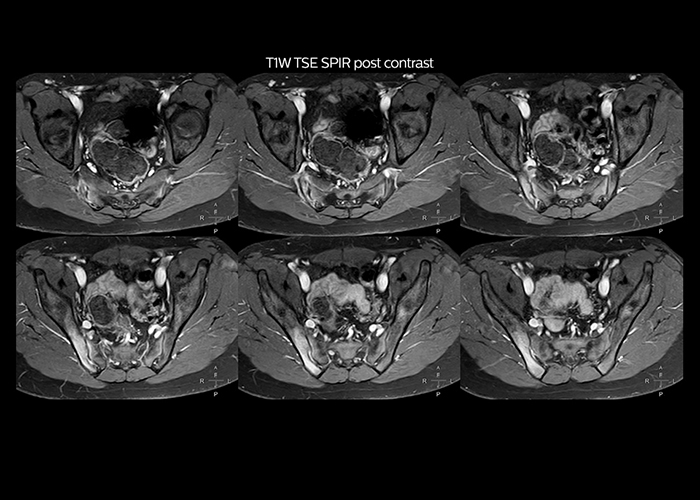

“To avoid coil changes we plan examinations of similar anatomies back to back, such as head and spine. Multiva helps us here a lot because coils don’t need to be changed frequently. Moreover, thanks to parallel imaging technology and 16-channel HeadSpineTorso and 8-channel MSK coils we are able to achieve excellent image quality. In this way Multiva helped us to increase both image quality and productivity.”

“Neurological cases, such as brain and spine imaging, represent the largest share in our MR scanning, followed by musculoskeletal cases. In general, we use simple and basic imaging protocols. But occasionally, we use advanced techniques for problematic cases if necessary.